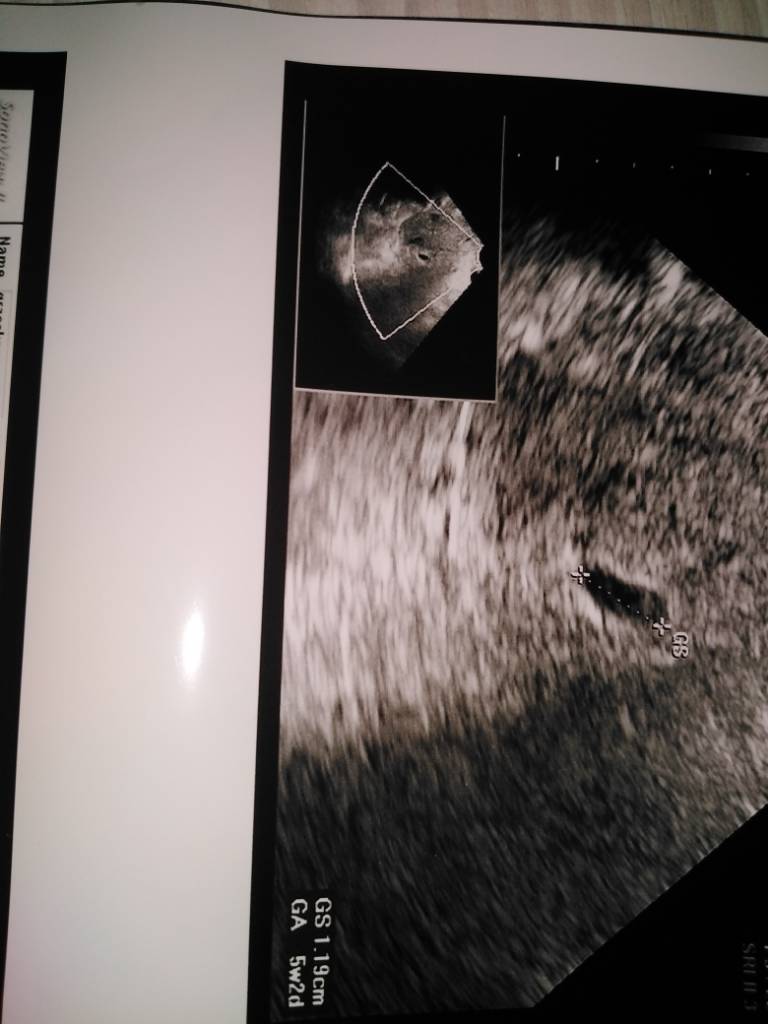

U mnie tak to wczoraj wyglądało, ginekolog mówi że w środu jest pęcherzyk żółtkowy, jednak martwi brak zarodka.

Zarodek pojawia się podobno 3-5 dni po pojawieniu pęcherzyka żółtkowego. Który to był tydzień u ciebie?

Wierze że na następnej wizycie zobaczysz już człowieczka z serduszkiem. Trzymam kciuki